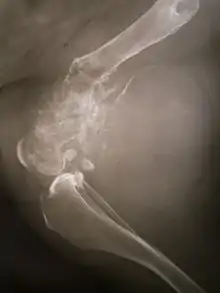

La tumeur est solide, dure, irrégulière, (décrite en « sapin » ou en « rayon de soleil » sur les examens aux rayons X) en raison des spicules tumorales d'os calcifiés rayonnant en angle droit. Ces angles droits forment ce que l'on appelle un triangle de Codman. Les tissus environnants sont infiltrés.

La tumeur peut être localisée à l'extrémité de l'os long. Le plus souvent, elle affecte l'extrémité proximale du tibia ou de l'humérus, ou l'extrémité distale du fémur. L'ostéosarcome tend à affecter les régions autour du genou dans 60 % des cas, dans 15 % des cas c'est autour de la hanche, 10 % à l'épaule et 8 % dans la mâchoire.

Découverte par le chirurgien Alexis Boyer en 1806[5], cette tumeur touche particulièrement les os longs comme le fémur (40 %), le tibia (20 %), le pelvis (10 %), l'humérus (8 %), les os de la face (< 10 %) [6].